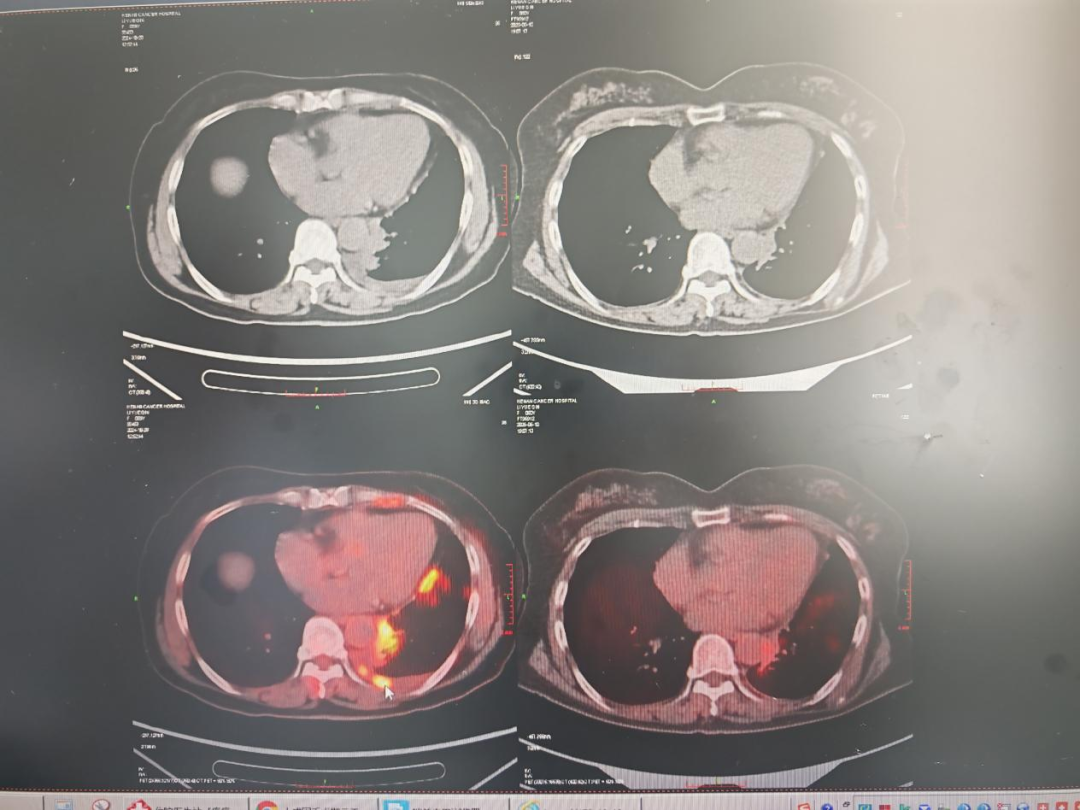

全身PET-CT(我院 2024.10.28):1.直肠中段壁局部增厚,代谢增高,疑恶性(直肠癌?);2.降结肠未端左旁结节状软组织影,代谢增高,多考虑转移;3.左下肺门处代谢活跃灶,呈软组织密度,多考虑恶性(肺癌?);左肺多发结代谢增高,考虑肺转移;右肺多发结节样及片状密度增高影,代谢未见异常,炎性?随诊;双肺少许炎症;左肺下叶局部肺不张;4.左侧锁骨上区、颈部双侧Ⅰ-Ⅲ 区、纵隔 1R、4、5、7区、双侧腋窝多发软组织结节,部分代谢增高,多考虑多发良性淋巴结伴部分炎性淋巴结;5.左侧胸膜(胸以隔、斜裂胸膜)多处不均匀增厚,代谢增高,考虑胸膜多发转移;左侧胸腔积液;6.左侧膈肌多增厚,代谢增高,考虑转移;左侧胸壁软组织多处代谢活跃灶,考虑转移;7.左侧肩胛骨局部呈混杂性骨质破坏,代谢增高,考虑骨转移。气管镜病理结果示:(左肺下叶背段盲检查)腺癌浸润。

影像检查:PET-CT(我院 2025/6/10)示:与我院2024.10.28 PET/CT对比:1.“直肠癌化疗后”直肠中段前壁较前变薄,代谢未见异常,符合治疗后明显好转表现;2.原降结肠末端左旁结节状软组织影,较前体积缩小,代谢未见异常,符合治疗后明显好转表现;腹、盆腔新见多发絮状、结节状密度增高影,部分与邻近肠管分界不清,代谢增高,考虑多发转移;3.左下肺门处代谢活跃灶,较前体积缩小,代谢较前减低,符合治疗后好转,但仍有肿瘤组织存活表现。

图1 术前PET-CT,提示胸膜转移